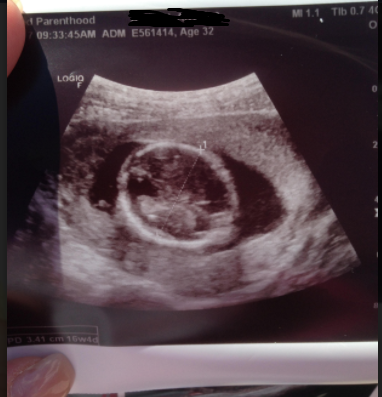

Below is the picture that the mobile unit printed out and gave Amara. You can clearly see the head, body, arm and hand of Amara’s preborn baby.

Amara came out of the mobile unit with a big smile on her face. She showed Whitehead the picture of her baby, exclaiming: “I can’t believe it! Look! It’s a whole baby!”

Before pro-lifers showed her the truth, Amara had no idea her baby was fully developed. Planned Parenthood had led her to believe her 16 week old child was just a circular blob of tissue.

Here are the two ultrasounds, side by side (left: Planned Parenthood; right: mobile ultrasound unit):